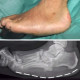

Pasien datang dengan keluhan kakinya bengkak, nyeri dan terlihat melengkung sejak beberapa bulan terakhir. Pasien didiagnosa dengan diabetes melitus sejak 5 tahun yang lalu. Namun, pasien mengaku jarang mengonsumsi obat diabetes dan tidak pernah kontrol ke dokter. Apa diagnosa yang tepat, ya?

Pasien dengan riwayat diabetes melitus dan disertai dengan bentuk deformitas pada kaki seperti yang ditunjukkan pada foto klinis dan xray lebih cocok dengan diagnosis Charcot Foot. Pada Charcot foot didapatkan adanya destruksi pada tulang yang diakibatkan vasculopathy dan neuropathy akibat diabetes. Sehingga bentuk kaki akan mengalami suatu deformitas akibat ada nya destruksi tulang.

Pada gambar x-ray tampak deformitas kaki Charcot. Kondisi ini merupakan kondisi progresif yang berdampak pada orang dengan neuropati yang sering terjadi pada pasien Diabetes. Tulang, sendi dan jaringan lunak pada kaki dan ankle menjadi rapuh, yang mengarah kepada fraktur, dislokasi dan deformitas yang signifikan seperti kaki “rocker-bottom”

Pada foto X-ray terlihat:

- Kolaps arkus medial kaki

- Disorganisasi dan destruksi tulang-tulang kaki

- Gambaran “rocker-bottom deformity”

Ini bukan gout, RA, ataupun osteoporosis.

Dari pilihan yang diberikan, diagnosis yang paling tepat adalah efek komplikasi dari Diabetes mellitus (dengan komplikasi Charcot foot / neuropathic arthropathy)